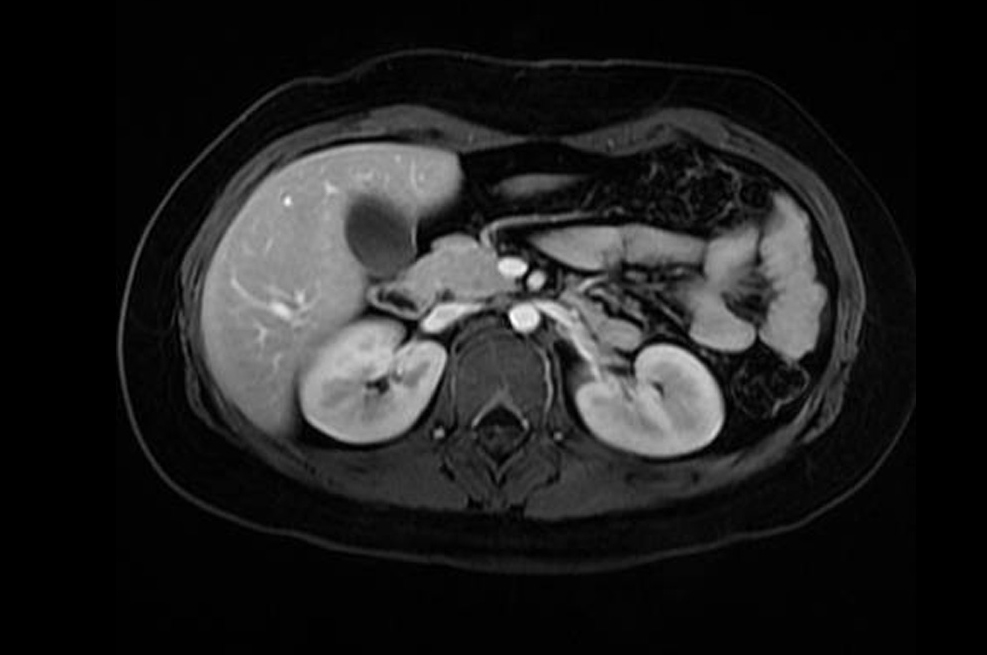

Resonancia magnética de abdomen es un examen de imagen que utiliza imanes y ondas de radio potentes para crear imágenes del interior del área abdominal. No emplea radiación (rayos X). Las imágenes por resonancia magnética solas se denominan cortes y se pueden almacenar en una computadora o imprimir en una película. Un examen produce docenas o algunas veces cientos de imágenes.

Una resonancia magnética del abdomen proporciona imágenes detalladas del área ventral desde muchos planos. Con frecuencia, se utiliza para clarificar hallazgos de radiografías o tomografías computarizadas previas.

• Flujo sanguíneo en el abdomen

• Vasos sanguíneos en el abdomen

Una resonancia magnética puede diferenciar tumores de tejidos normales. Esto puede ayudarle al médico a conocer más acerca del tumor, como el tamaño, la gravedad y la propagación, lo cual se denomina estadificación.